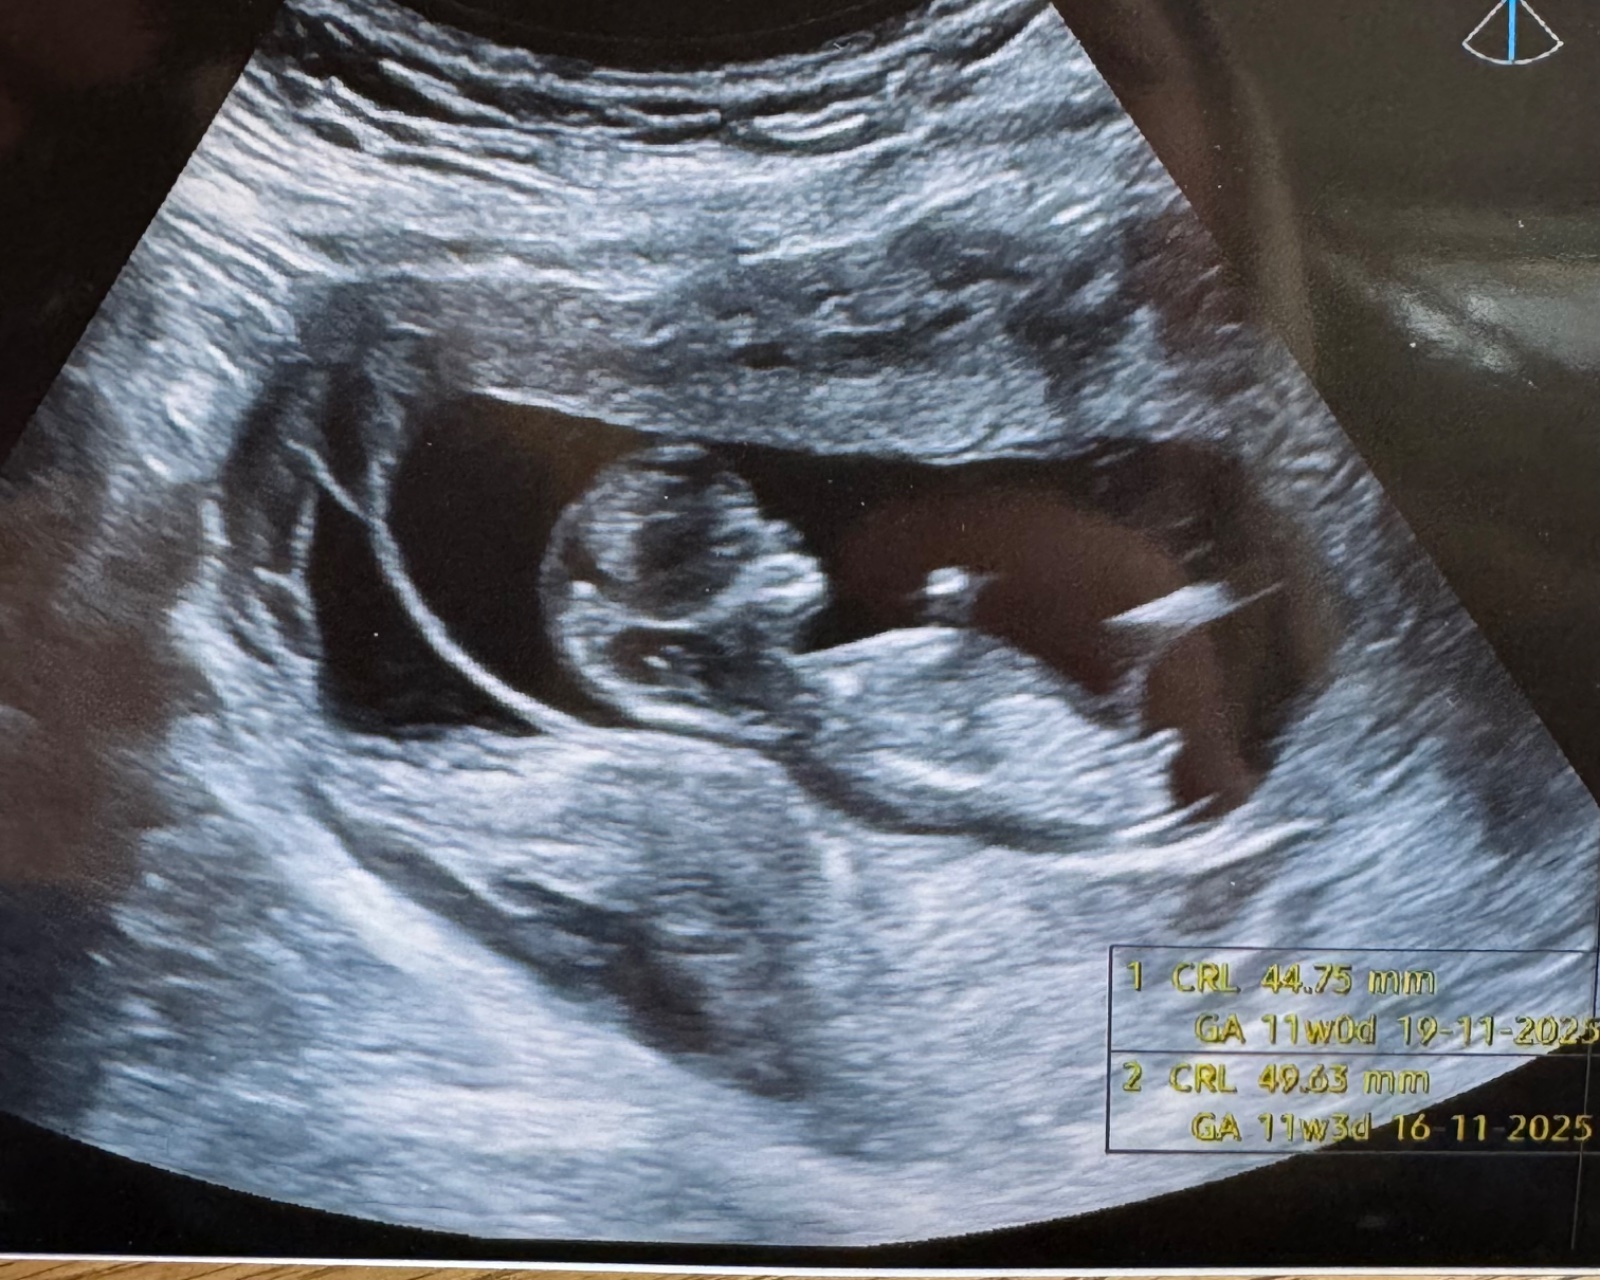

Ahoj, nevíte co by to mohlo být u me? 😁

@markeetaaa24 Miminko 🙂.

Obávám se, že to, co tak příhodně trčí v oblasti mezi nožičkama, je pupeční šňůra (je vidět linie jdoucí rovně velmi daleko přes tělíčko) a partie, podle kterých se obvykle pohlaví určuje, jsou tím pádem vlastně mimo záběr.